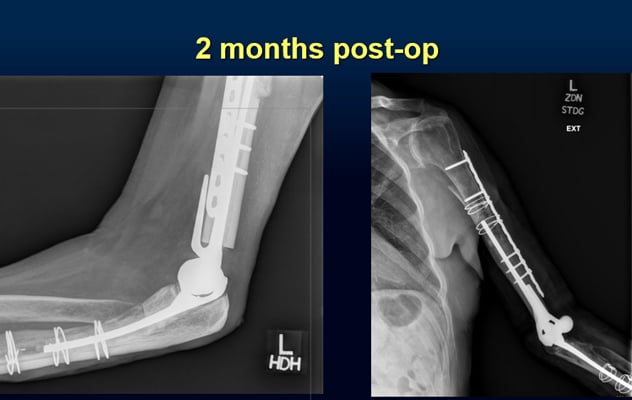

Two months post-op

A patient's elbow at two months post-op following revision TEA.

Three months postoperatively, the patient's hand and elbow were functional. As the patient thought he was facing amputation before meeting Dr. Morrey, he was enormously grateful, seeing his results. He is now two years after his reconstructive surgery and extremely pleased with his results.